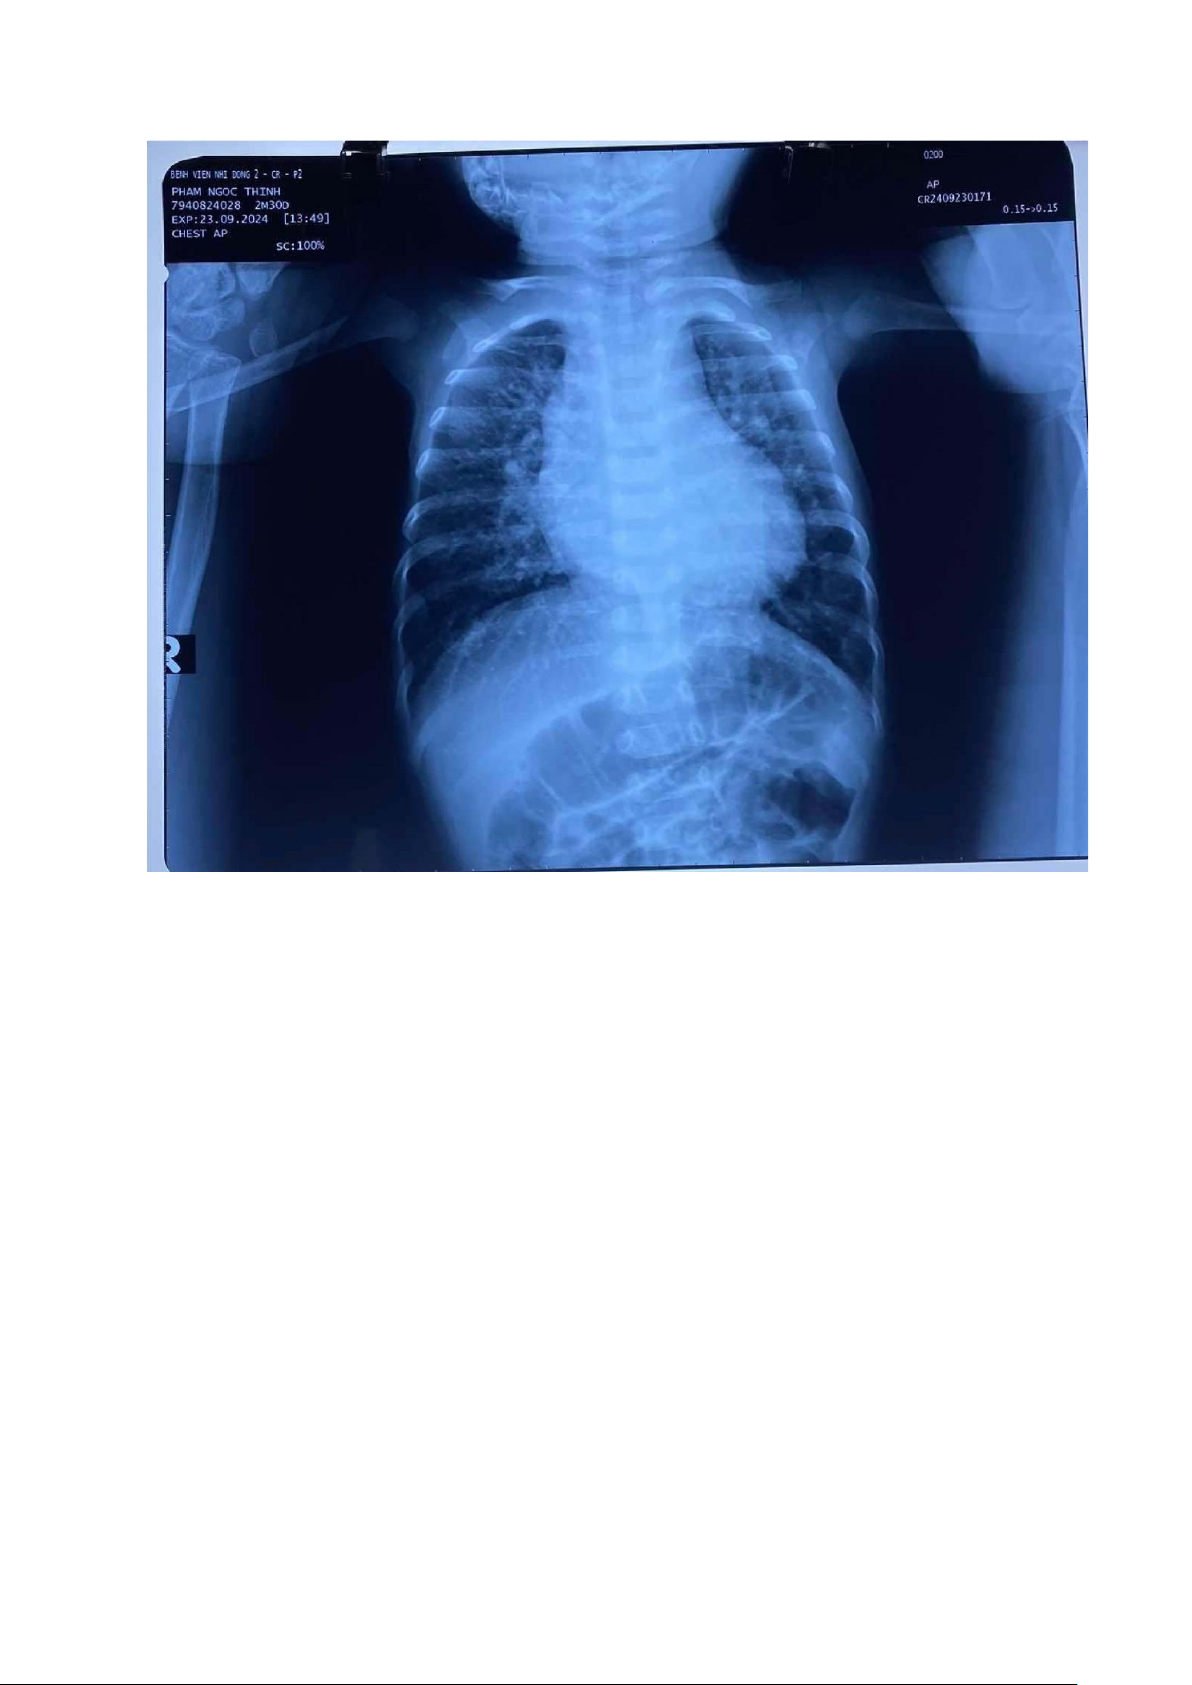

- Ferritin tăng 670 ug/L -> ề nghị thêm iện di Hb. 4. X-quang 19/9: 1. vị trí tim:

+ Situs solitus + Levocardia2. tuần hoàn phổi:+ rốn phổi ậm, tuần hoàn

phổi ra ⅓ ngoài 2 bên phế trường

→ tăng tuần hoàn phổi chủ ộng

2. kích thước tim và các cung tim 3. hình dạng bóng tim 4. 23/9: 5. Cấy àm: âm tính XII. Chẩn oán xác ịnh XIII. Điều trị 1. Maxapin 1g 210mg x 3 (TMC)